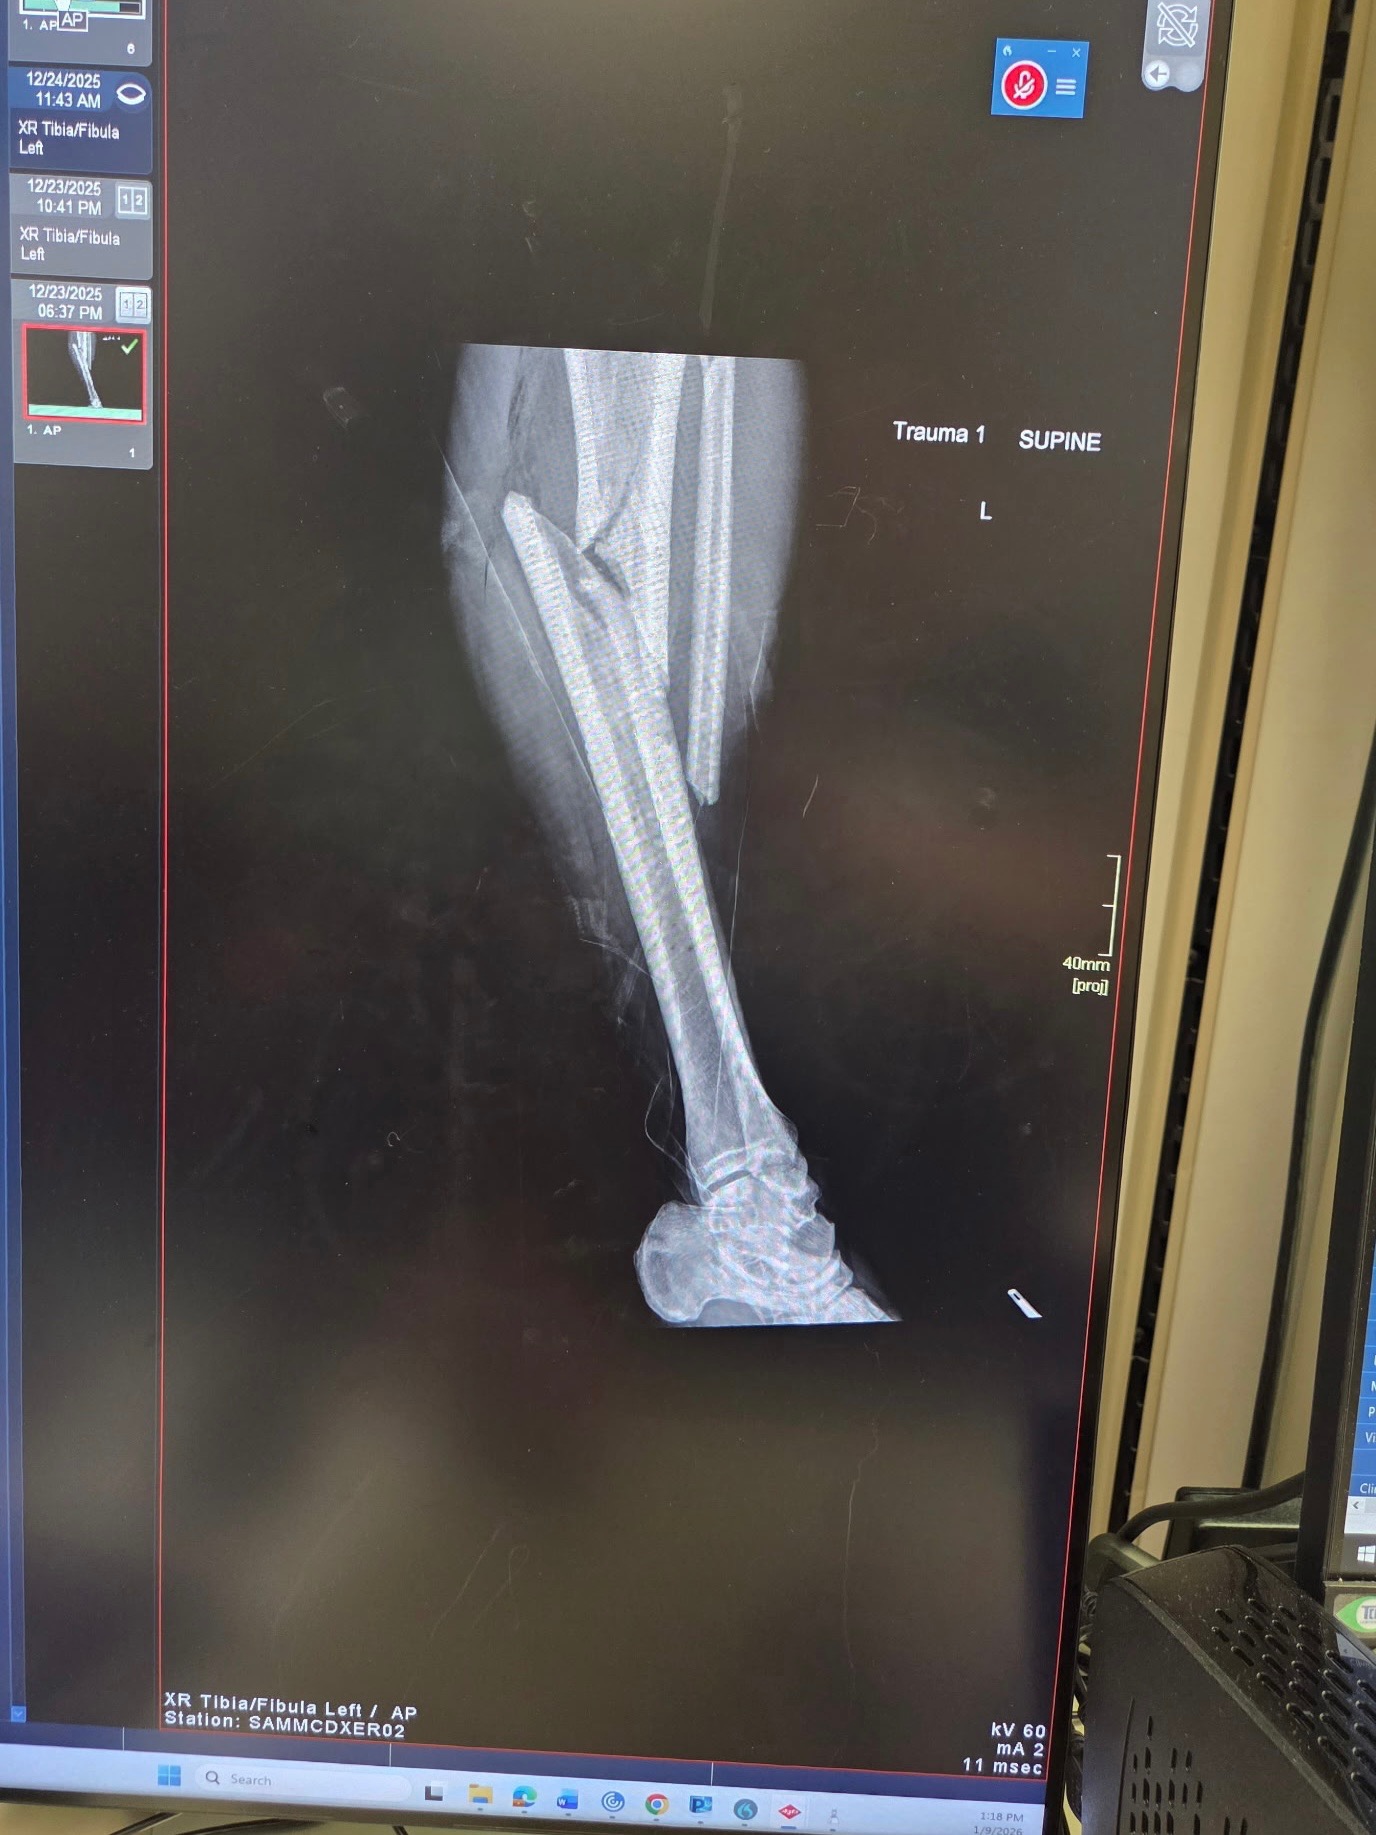

He was then rushed to BAMC Trauma Center at Fort Sam Houston, where surgeons were able to stabilize and rebuild his leg using a complex system of metal rods, bolts, and screws. While the surgery was a success, we are now at high stakes while monitoring for infection as the risk of him losing his leg is still very real.